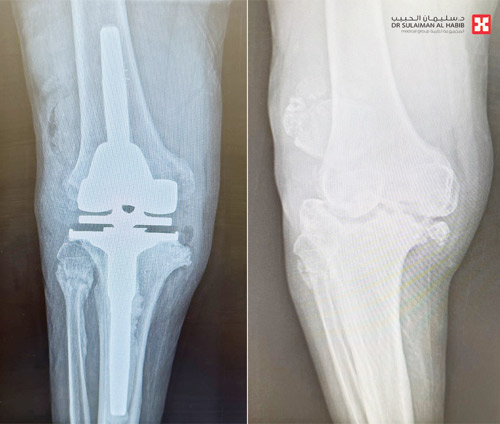

وقال د. عبدالله الشهراني استشاري جراحة العظام واستبدال المفاصل الصناعية، رئيس الفريق الطبي المعالج، إن المراجع جاء إلى المستشفى وهو يشكو من أعراض كالآلام والتورم وتغير شكل الركبة، بالإضافة إلى صعوبة الحركة، وأجريت له سلسلة من الفحوصات الدقيقة، كالتصوير بالرنين المغناطيسي والأشعة السينية، وبيَّنت النتائج وجود تآكل في عظمتى المفصل، وخلل في حركة عظمة رأس الركبة مع الخشونة والاحتكاك الحاد، وكذلك ارتخاء شديد في أربطة الركبة الجانبية، وتلف غضاريف المفصل.

وقام الفريق الطبي بدراسة الحالة بدقة على ضوء نتائج الفحوصات، وخلص إلى أن هناك ضرورة لإجراء عملية لاستبدال المفصل، بآخر صناعي يتوافق مع معطيات التشخيص الطبي للحالة، وبعد اتخاذ الترتيبات والتحضيرات اللازمة أجريت له عملية تم فيها، استبدال مفصل الركبة بآخر صناعي يناسب الحالة، بالاستعانة بأحدث الأجهزة الطبية، وتكلَّلت العملية التي استمرت لمدة «90» دقيقة، ولله الحمد بالنجاح، وتمكن المراجع من المشي على قدميه بعد «5» ساعات من العملية، وغادر المستشفى بحالة صحية جيدة بعد «7» أيام.